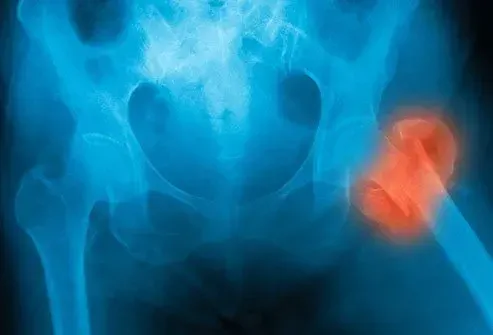

Maladie des artères périphériques (PAD)

Le pad est comme la CAO, mais cela affecte les vaisseaux sanguins plus loin de votre cœur comme ceux de vos bras de bras la tête ou l'estomac. Vous pourriez souvent avoir de la douleur ou des crampes dans vos jambes lorsque vous marchez ou montez les escaliers. Cela peut également vous fatiguer. La douleur peut disparaître lorsque vous vous reposez et revenez lorsque vous déménagez. Le coussin non traité laissé pourrait apporter des problèmes plus graves comme les ulcères de l'AVC et la perte de circulation dans vos jambes, ce qui peut provoquer une amputation.